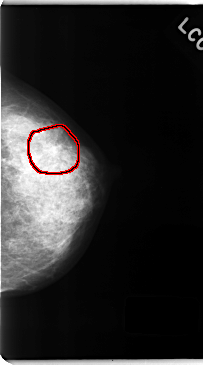

C_0142_1.LEFT_CC

LEFT_CC LINES 4736 PIXELS_PER_LINE 2632 BITS_PER_PIXEL 12 RESOLUTION 50 OVERLAY

FILE: C_0142_1.LEFT_CC.OVERLAY

TOTAL_ABNORMALITIES 1

ABNORMALITY 1

LESION_TYPE MASS SHAPE IRREGULAR MARGINS SPICULATED

ASSESSMENT 5

SUBTLETY 4

PATHOLOGY MALIGNANT

TOTAL_OUTLINES 1

BOUNDARY